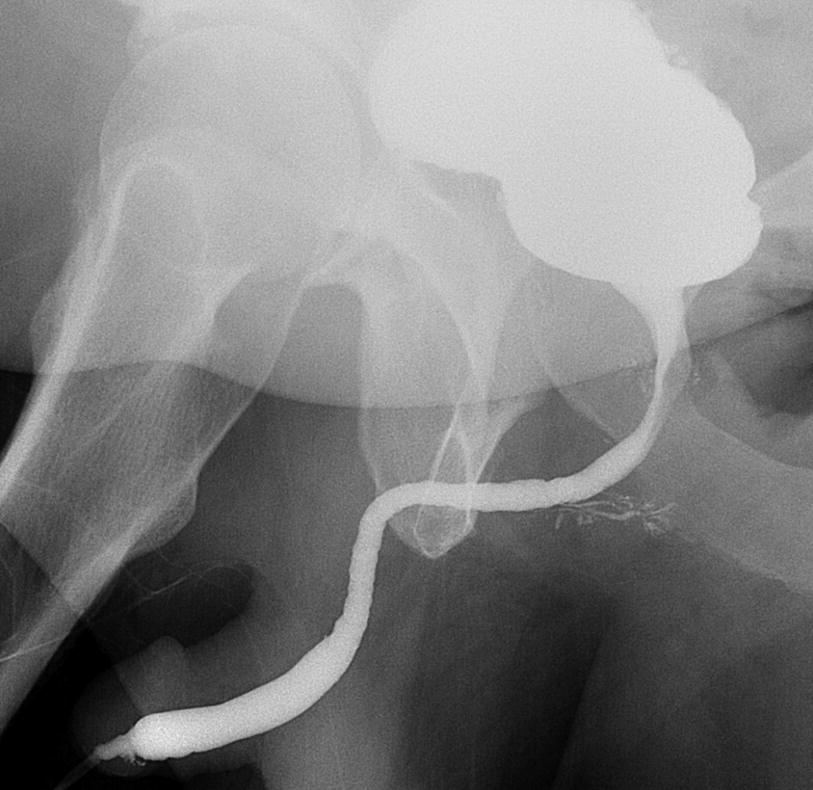

VCUG showing a tight fossa navicularis with mild irregularities within the bulbar urethra. (Imaging courtesy of Joseph Pariser, MD)